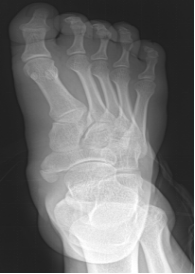

足骨

包括跗骨、跖骨和趾骨。跗骨共7块,分前、中、后列。后列包括距骨和跟骨;中列为距骨前方的足舟骨;前列为内侧楔骨、中间楔骨、外侧楔骨及跟骨前方的骰骨

跖骨,共5块,近端为底,与跗骨相接;中间为体,远端称头,与近节趾骨底相接

趾骨,共14块,踇趾为2节,其余各趾为3节。分为近节趾骨,中节趾骨和远节趾骨。每节趾骨近端为底,中间部为体,远端为滑车

先天性马蹄内翻足

足舟骨骨折;跖骨骨折;楔骨骨折;跟骨骨折